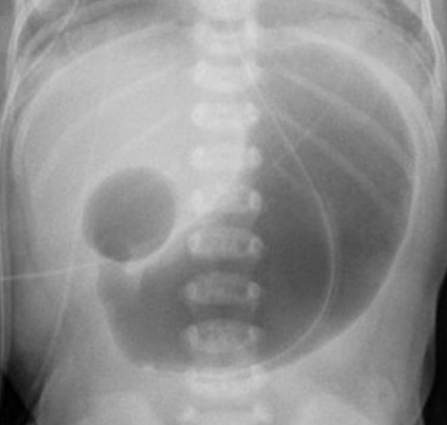

Double bubble sign which is a feature of the _____ atresia.